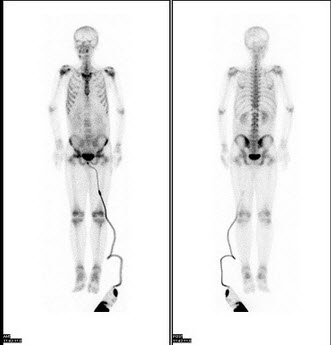

82、多项选择题

男,21岁,无痛血尿半年。体检恶病质面容。行全身骨显像如图。对此描述正确的是()

A.大致正常的骨影像

B.多发性骨转移瘤

C.胸12椎体“冷区”,可能为溶骨性破坏

D.胸12椎体骨转移瘤

E.原发病可能是泌尿系统恶性肿瘤